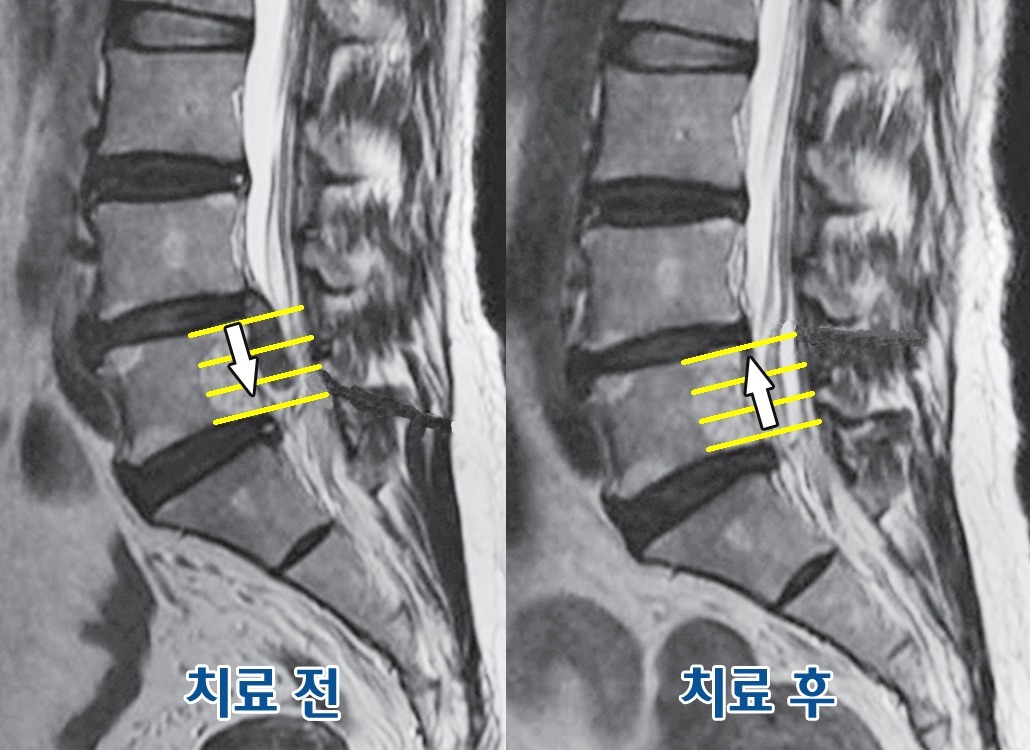

허리디스크증상이 악화되면, 외과적 수술이 필요할 수도 있으며, 이러한 상황을 피하기 위해 조기 개입이 필요합니다. 통증 관리에는 물리치료, 약물치료, 운동 요법 등이 포함될 수 있으며, 이러한 방법들을 적절히 활용하여 증상을 완화할 수 있습니다.

물리치료는 허리디스크로 인한 통증 관리를 위해 효과적인 방법 중 하나입니다. 전문 물리치료사의 지도 아래, 스트레칭과 강화 운동을 통해 근육을 강화하고 유연성을 높일 수 있습니다. 이러한 치료는 회복을 촉진하고, 통증을 줄이는 데 효과적입니다.

운동 요법은 허리디스크 증상이 있는 환자에게 큰 도움이 될 수 있습니다. 전문가의 지도 아래에 적절한 운동을 통해 근력을 키우고, 허리의 안정성을 높일 수 있습니다. 이는 통증을 줄이고 재발을 예방하는 데 기여할 수 있습니다.